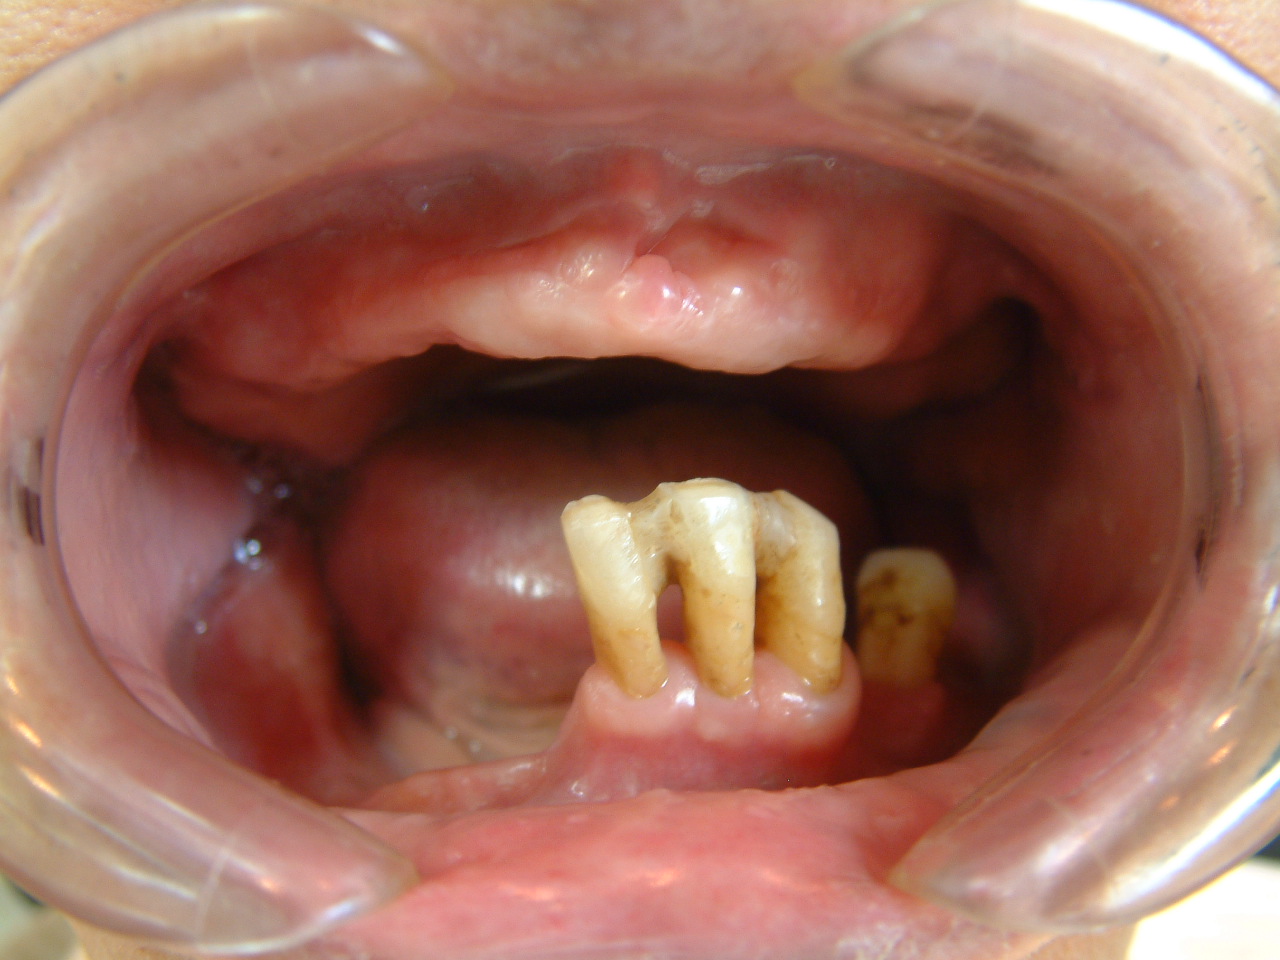

Photo-11.歯の喪失

thumb-1

57才男性(既往歴なし):複数の医院で受診するも歯周病は改善せず、某国立大学・歯学部歯周病科において歯周外科手術(フラップオペ)を受けたが3回目の手術後、菌血症のため体調不良になりかかりつけの内科医よりドクターストップとなり、当院に転医。初診時、すでに大半の歯は保存不可能な状態にあり、位相差顕微鏡検査やDNA検査においても大量の細菌が検出された。

すでに歯の保存は困難であり早期の抜歯をすすめるが同意が得られないために病原菌除菌(溶菌・除去)、レーザー治療、食事療法などにより炎症症状を消失後、数年かけて抜歯を行なったもの。患者さんに持病はなくとも病因である病原菌除菌を歯周病の早期段階で実施されていない場合、後に歯周外科手術をおこなっても、このような結果になります。